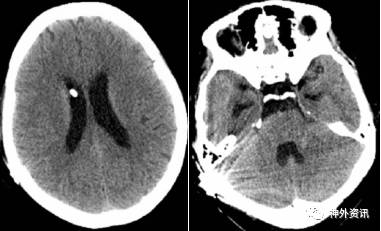

头颅CT平扫、头颅CTA及头颅MRV(图4)未见明显异常。余血化验未见明显异常。浅表淋巴结超声、胸片、心电图等相关检查均未见明显异常。

图 4. MRV 未见明显异常。